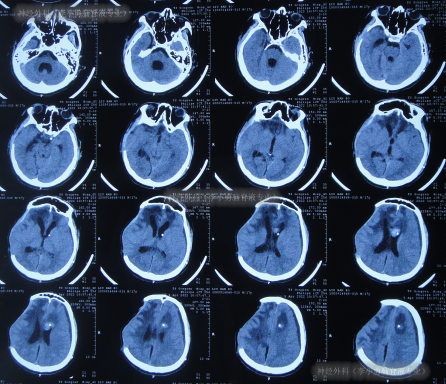

去骨瓣减压+血肿清除术后第2天即2022年2月3日,头颅CT示出血有增多(图-3)。

图-3:2022年2月3日头颅CT

术后3天即2022年2月4日,患者苏醒,能言语,但遗留左侧肢体不能活动,低钠血症,查头颅CT示仍有较多积血(图-4)。

图-4:2022年2月4日头颅CT